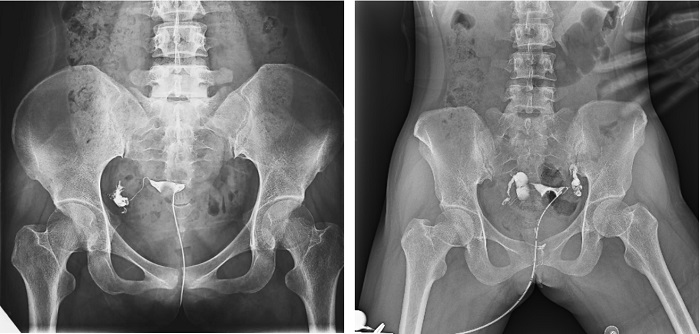

子宮輸卵管造影檢查損傷小,準(zhǔn)確率高,是婦科檢查的常用方法。利用動態(tài)DRF進(jìn)行子宮輸卵管造影檢查,大大超越了過去的檢查技術(shù),更加精準(zhǔn)高效。動態(tài)DRF矩形采集面積大,一次曝光即可顯示整個盆腔,大幅減少觀察時間,可控的瞬時照射避免受檢者吸收過多X線,對育齡期女性檢查尤為重要??稍谠煊皠┝鲃拥倪^程中完成拍片,抓拍到關(guān)鍵圖像,幫助醫(yī)生更加清楚地了解到管腔的具體通暢情況及堵塞部位,提高診斷的精準(zhǔn)性。

▲輸卵管造影

普利德動態(tài)平板DRF床體智能化程度更高,在進(jìn)行子宮輸卵管造影檢查時,醫(yī)生可以通過調(diào)整床體起倒角度精準(zhǔn)控制造影劑的流動方向和速度,并根據(jù)造影劑在輸卵管及盆腔里的顯影準(zhǔn)確判斷輸卵管堵塞部位、程度及性質(zhì),極大提高了拍片效率和診斷的精準(zhǔn)性。